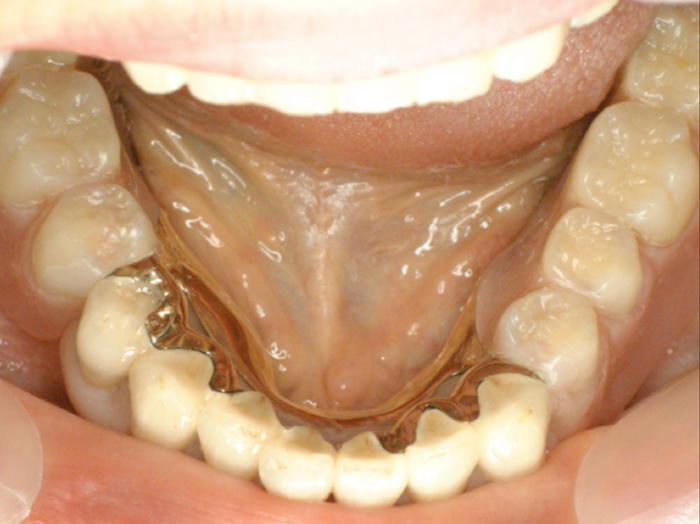

| ●本ケースは、上下顎全歯で患者さんの天然歯が4歯だけ残った症例でした。 結局、上顎にはメタルセラミックスブリッジ補綴を施し、下顎はチャネルショルダーアタッチメントと エクストラコロナル・自家製棒状アタッチメントによるミリング・コンビネーションデンチャーを装備 しています。 ●チャネルショルダーアタッチメントおよび棒状アタッチメントのテクニックに関しては「論文」編 のPDFファイルをご参照くださいませ。 また、製作工程の詳細は「臨床例:補綴用実践的ワックスアップ手順を追う! (コンビ01)」 に良く似た症例を掲載しましたので、ご供覧ください。

| ●下顎右大小臼歯から左犬歯まではメタルセラミックスの連続冠で補綴し、 右大小臼歯、右犬歯および左犬歯、左側切歯の4歯の舌側面にチャネルショルダー内冠 と棒状アタッチメントをミリング加工した。 チャネルショルダー外冠および棒状アタッチメントはパラレルミリング加工しているので、 精密な摩擦抵抗力を持った適合精度が求められます。 内冠の長径および幅径によっても、鋳造システムによる埋没工程の混液比や混水比が 変わってきますので、「コンビネーション用のチェックリスト」を制作し、データを分析しよう。